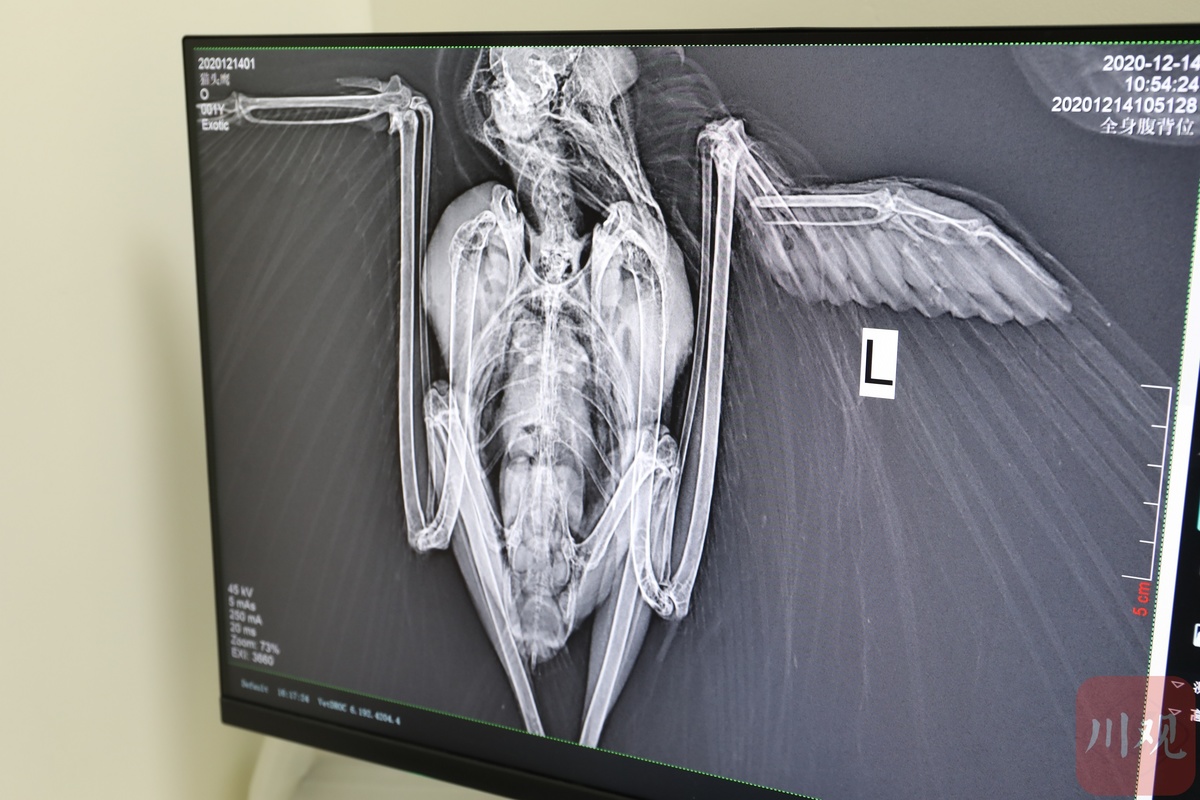

猴面猫头鹰X光片。 杨尚威摄

“通过X光照片发现它的左翅,相当于人的手桡骨部骨折了,我们只好用钢钉,也就是髓内针把它的断骨部分接好、固定,并配合后期的消炎治疗。”救治猴面猫头鹰的乐宠宠物医院动物医生余晓平介绍,受伤的这只猴面毛头鹰已成年,加上受伤受了惊吓,出现了拒食现象,目前医院只能人工喂食喂水。